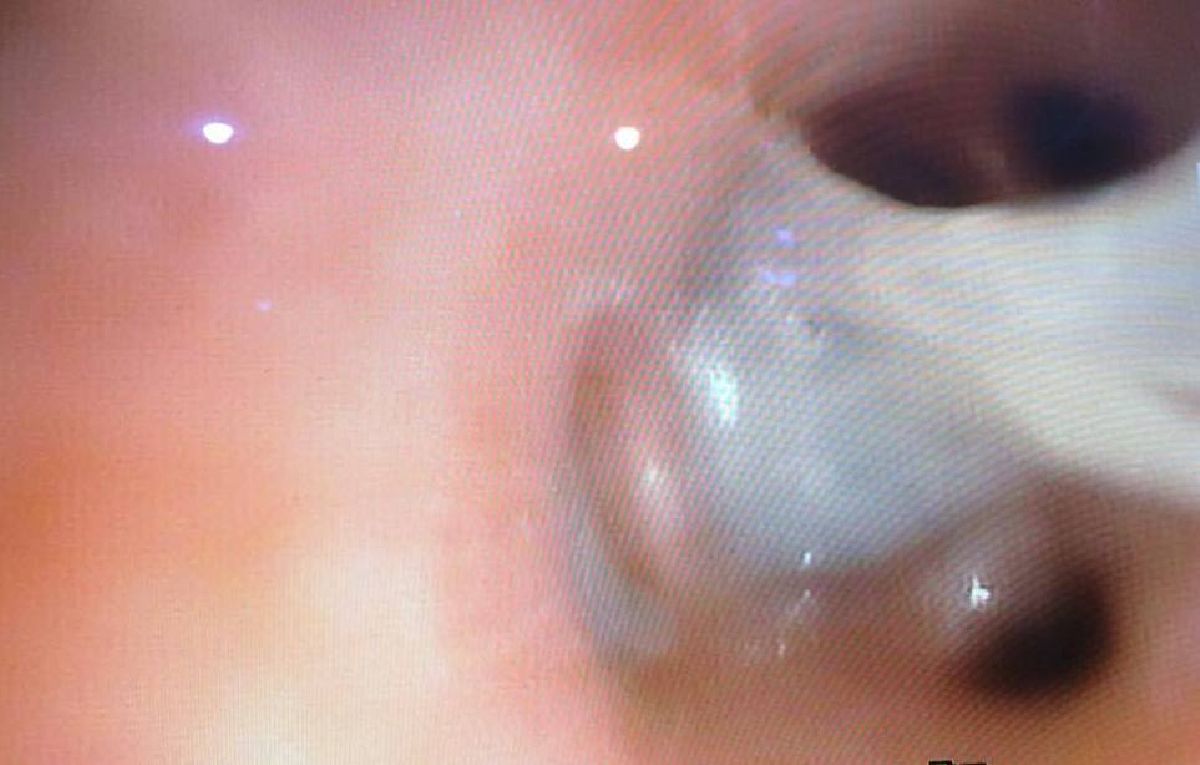

Zakładam tę zbiórkę z prośbą o pomoc w wykonaniu badania bronchoskopii układu oddechowego ( oskrzeli) by mieć obraz jak jego oskrzela w tej chwili wyglądają, poprzednim razem była konieczność odessania wydzieliny która znajdowała się w oskrzelach ( zdjęcia dołączone) koszt badania łącznie z podaniem narkozy to 500 zł plus przepisane odpowiednie leki.